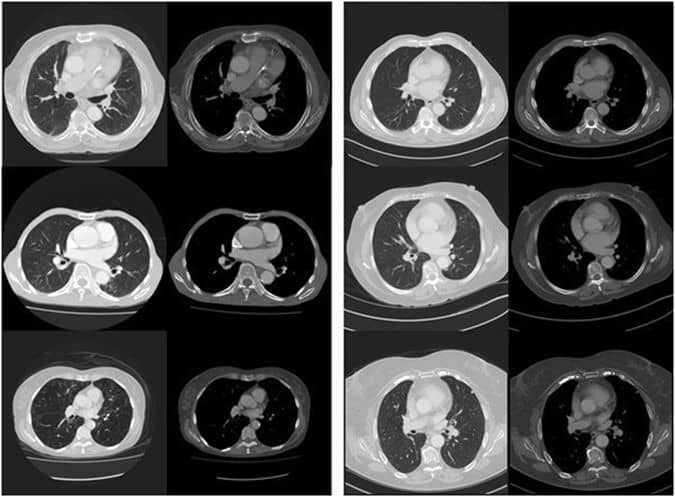

研究人员使用48例患者的CT扫描开发了该系统,并使用收集的数据来创建诊断算法,以预测患者是否会在未来五年内死亡。预测已经69%到目前为止准确,这与人类医生的预测大致相同。这项研究是采用医学图像和人工智能的研究之一,并在自然杂志科学报告。

但是这些计算机确实以更快的速度工作,并且几乎无时间可以分析大量扫描。这个想法很有用,因为投射患者的死亡可能会增加生命的可能性,因为它可以及时确保适当的医疗护理。该算法使用深度学习系统使用16,000多个图像功能,并突出显示潜在疾病。这种熟练程度将需要医生多年的练习,而机器立即进行适应。